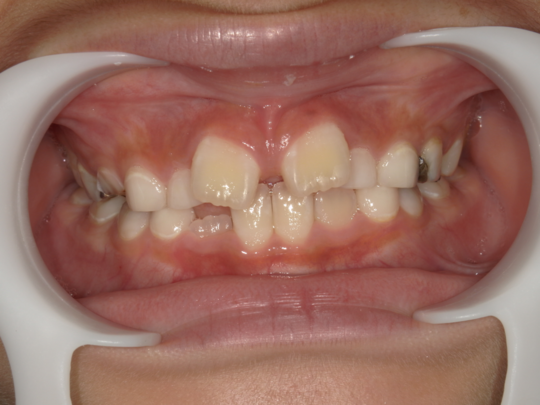

治療前

治療説明 歯科矯正で取り外し可能な矯正方法である床矯正で治療しました

治療期間 2年1か月

治療費200000 円

治療後

治療の副作用(リスク)歯の動き方には個人差があり、予想された治療期間が延長する可能性があります。。床矯正の使用状況、矯正歯科治療には患者さんの協力が必要であり、それらが治療結果や治療期間に影響します。2次矯正が必要になる場合もあります。